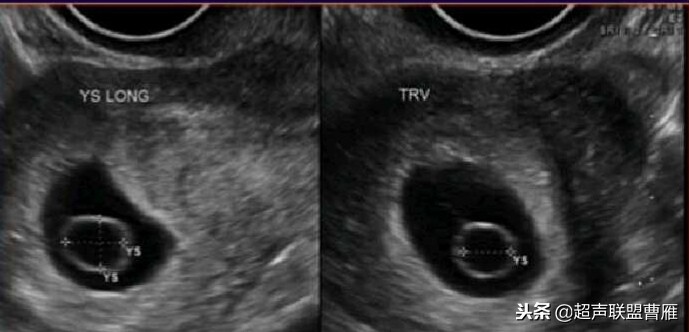

· 正常情况下,卵黄囊中央表现为无回声,周边为厚薄均一、边界清晰的环形高回声。

· 正常卵黄囊内径一般在3-5mm,妊娠第5-10周逐渐增大,而10周后逐渐减小,一般12周前消失。

· 当妊娠囊平均直径在5-6mm时,经阴道超声即可发现卵黄囊

妊娠37天超声检查卵黄囊可以显示,羊膜腔及胚胎不能显示

妊娠37天出现卵黄囊

在妊娠妊娠38天前后(36-40)天可以见到卵黄囊。 孕囊在6-9mm的可以见到其中有卵黄囊。

有的图像卵黄囊YS只是两条平行的细短线

正常早孕卵黄囊声像图